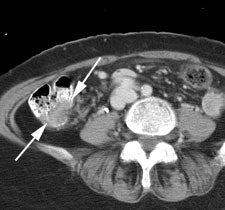

Bladder cancer: Dilute urinary activity in this patient's bladder allowed accurate detection of their bladder cancer (white arrows on CT, black arrows on PET scan). In general, urinary excretion of FDG limits evaluation of urinary tract malignancies, however, hydration and diuresis can improve diagnostic accuracy. |

|

|